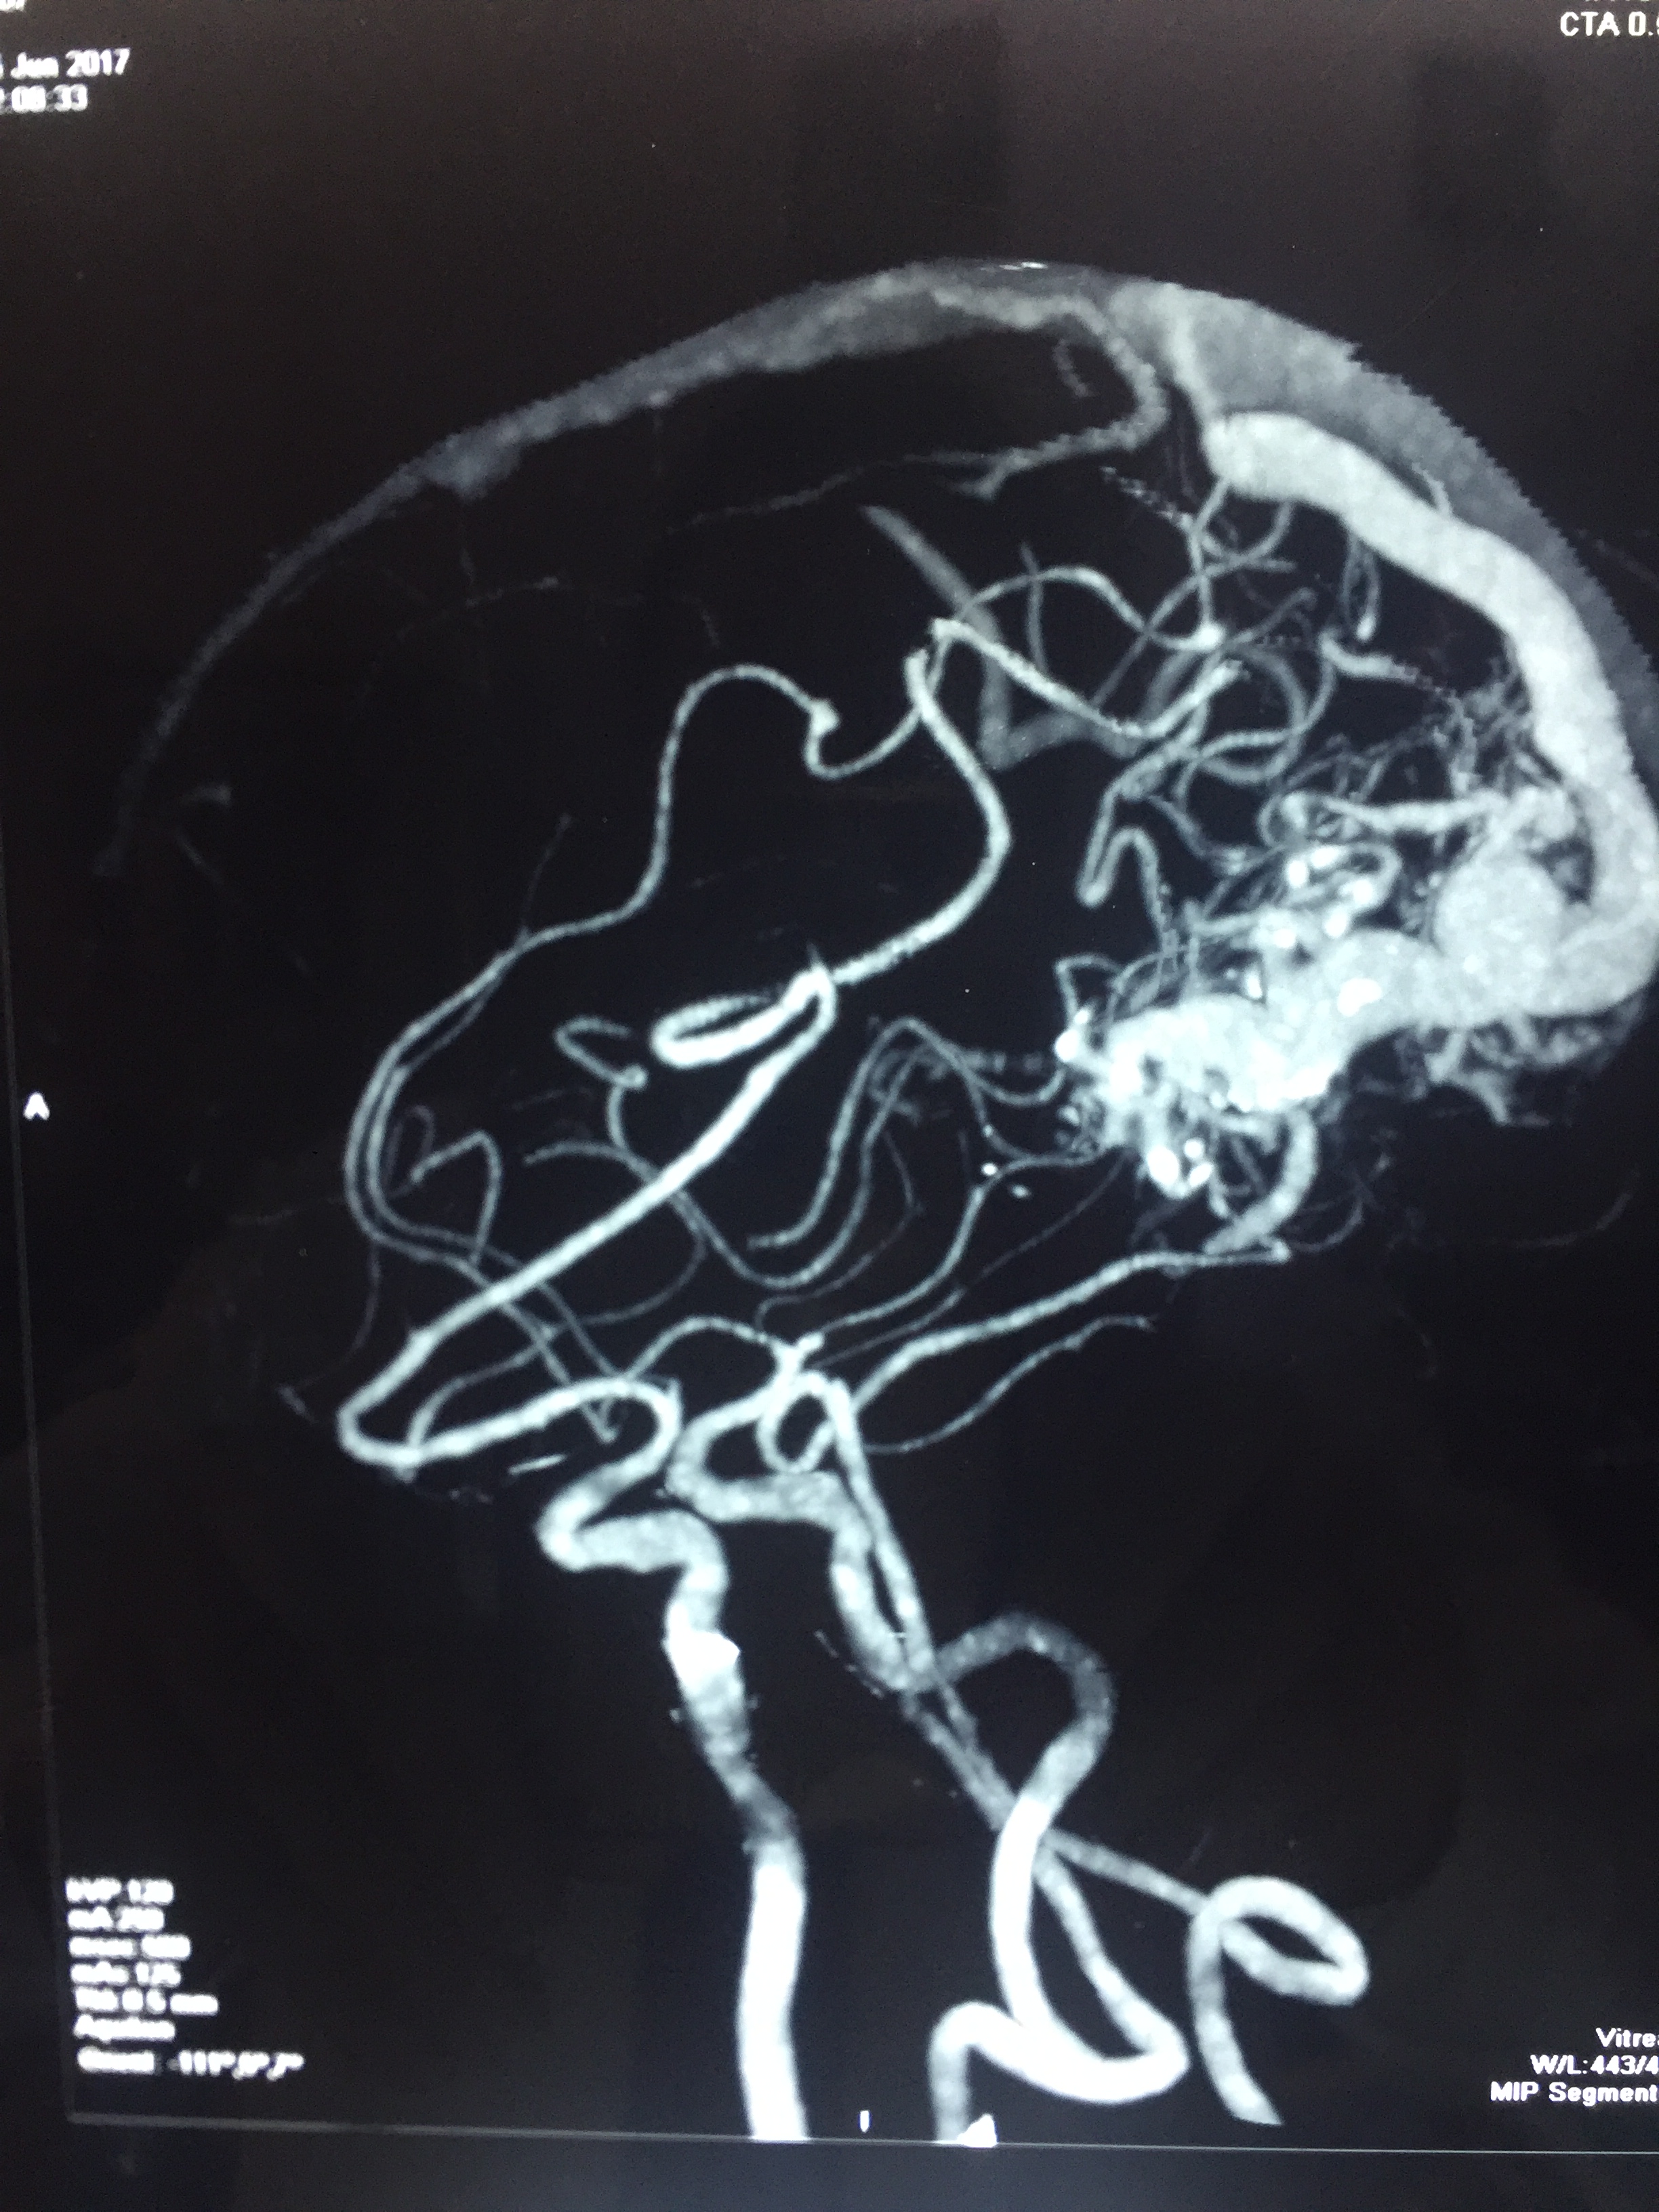

Lt. Occipital AVM : Surgery - Microsurgical excision of AVM (Lt. Occipital Grade IV AVM)